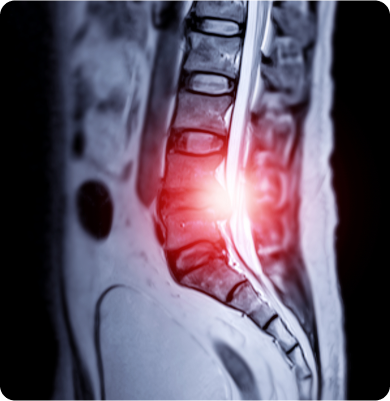

척추 뼈 사이에 위치한 디스크가 탈출하거나 부풀어 나와 신경을 압박해 통증을 유발하는 질환

나이가 들면서 디스크 퇴화가 진행되거나 잘못된 자세나 반복적인 허리 사용으로 발생할 수 있습니다. 갑작스러운 외상이나 사고도 원인이 될 수 있습니다.

신경이 지나가는 통로인 척추관이 좁아져 신경을 압박하는 질환

노화에 따라 디스크의 퇴행, 인대의 비후, 관절의 퇴행성 변화 등으로 척추관이 좁아지며 신경을 압박하게 됩니다. 또한 과거 외상이나 수술, 선천적 요인에 의해서도 발생할 수 있습니다.

척추의 뼈가 압력에 의해 눌려서 골절되는 질환

골다공증, 외상(교통사고나 낙상), 급격한 자세 변화 등으로 인해 척추에 과도한 압력이 가해져 발생하며 골밀도가 감소되었을 때에도 충분히 발생할 수 있습니다.

척추 뼈가 정상 위치에서 앞으로 밀려나가면서 발생하는 질환

주로 척추의 퇴행성 변화나 외상에 의해 나타나며 선천적인 척추 기형이나 유전적 요인도 원인이 될 수 있습니다.